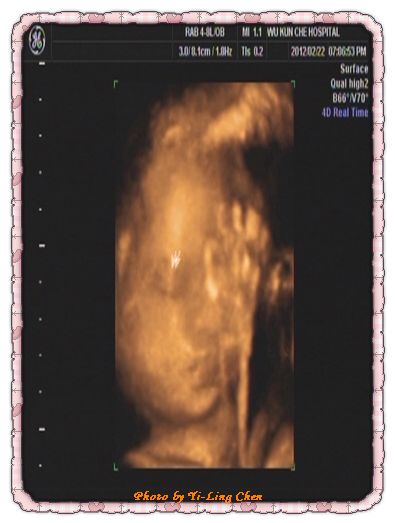

4D超音波可說是現在很先進的技術,也是要自費的

但是,問過幾位醫生,他們都一致說“4D只是讓爸媽看好玩的,沒有任何醫學上的實用”

基於這個原因,我一開始就不打算做4D超音波。

直到上次參加媽媽教室,有一張表格,只要填了就可以免費做4D超音波檢查

想說是免費的,就抱著玩票的性質,來看看4D超音波下的土豆吧!

4D超音波真的是玩票性質多啦!

醫生的講解也沒有像大醫院的醫生來的仔細

所以,4D超音波,有興趣的準爸爸和準媽媽們可以去照照看。

另外,昨天的土豆已經有30週大了,預估體重有1300克了。

而且,土豆已經就位了,也就是說我已經符合自然產的要素了。